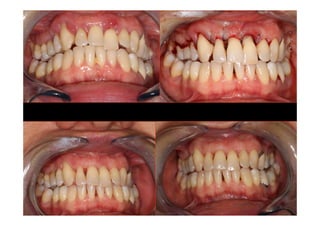

BASELINE

MODIFED WIDMAN FLAP

MODIFIED WF

1 év POSTOP.

(MWF)

Baseline X-ray

Periodontal charting